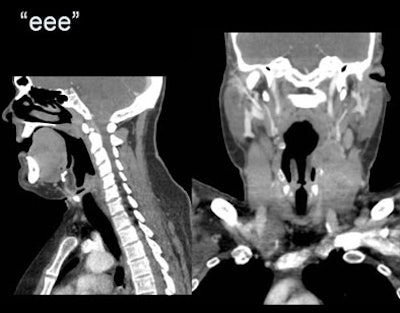

| Using the "eee" technique at right, the laryngeal ventricle is filled with air in the same squamous cell carcinoma patient scanned postchemotherapy. |